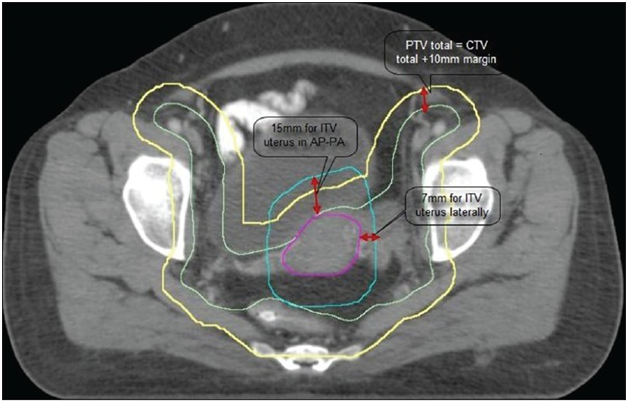

CT images archived from PACS were contoured with normal structures such as Rectum, Urinary Bladder, Intestines, Left and right femoral bones using an automatic edge detection algorithm using 3D slicer software in an independent system (Figure 1). And the Gross tumor volume, Clinical Target Volume, high risk/low risk tumor volumes were delineated with semi automatic algorithm under the supervision of experienced radiation oncologists. A Combined (MATLAB and C++) code was generated using grey scale differentiations and contoured volumes to extract the features. These features can be used as predictive models for outcome prediction, distant metastasis risk analysis and genetics assessment, when a new patient data was given as input (Figure 2).

Figure 1 Gross tumor volume.